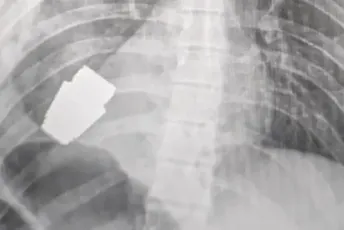

Operaciji su prisustvovala dva deminera koji su vodili računa da se eksplozivnom napravom pažljivo rukuje, rekla je zamjenica ukrajinskog ministra odbrane Hana Malijar, koja je na internet postavila fotografiju rendgenskog snimka na kojem se vidi granata u vojnikovom tijelu.

„Vojni ljekari su sproveli operaciju tokom koje su uklonili VOG granatu, koja srećom nije eksplodirala, iz tijela vojnika“, napisala je ona na Fejsbuku, prenosi Gardijan.

„Neeksplodirani dio granate je izvađen iz predjela ispod srca. Iako nije eksplodirala, granata je imala eksploziv“, napisao je Geraščenko na Telegramu.